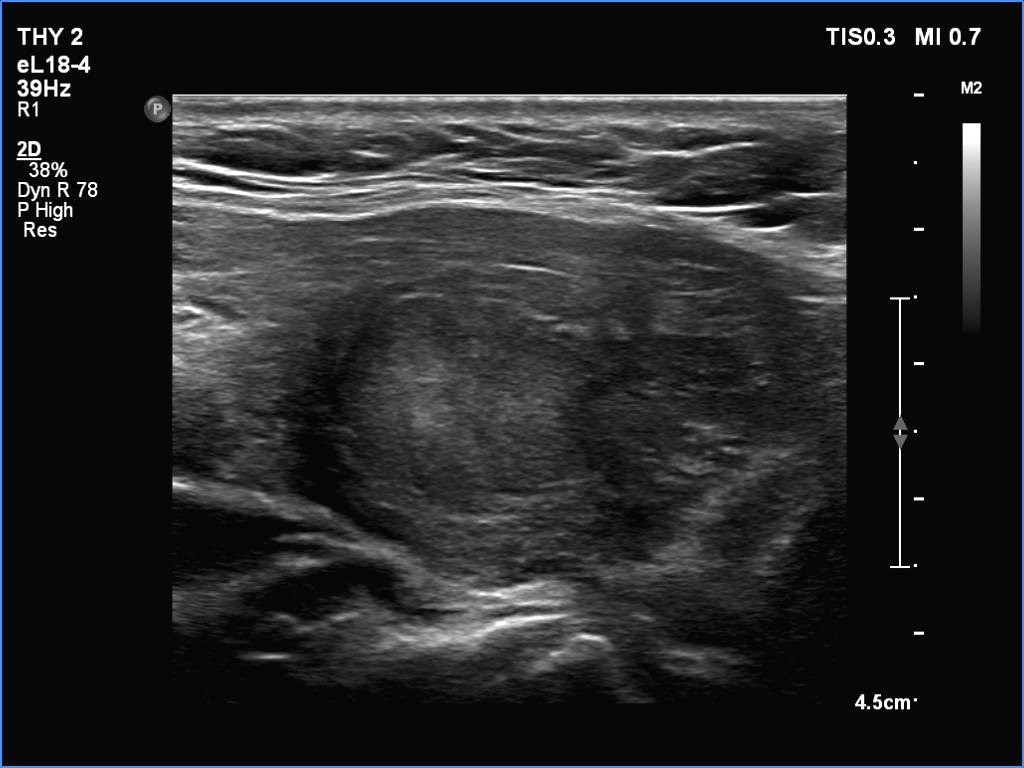

Ultrasonography. The thyroid was partly minimally/moderately, partly very hypoechoic. There was a nodule in the middle of the left lobe. It was lighter than the extranodular part but darker than a normal, healthy thyroid.

Comments. All but one society suggest to compare the nodule' echogenicity to the non-nodular part. In this case, the nodule should be regarded as iso/hyperechoic. If we accept the suggestion of the 2023 ETA guideline, then we should consider the nodule as minimally/moderately hypoechoic because the reference tissue in the ETA is the normal, healthy thyroid and not the diseased, extranodular part.